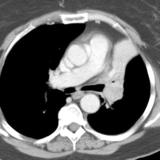

LUL Collapse Case 6 CT

Date: 02/19/2004

Views: 3122